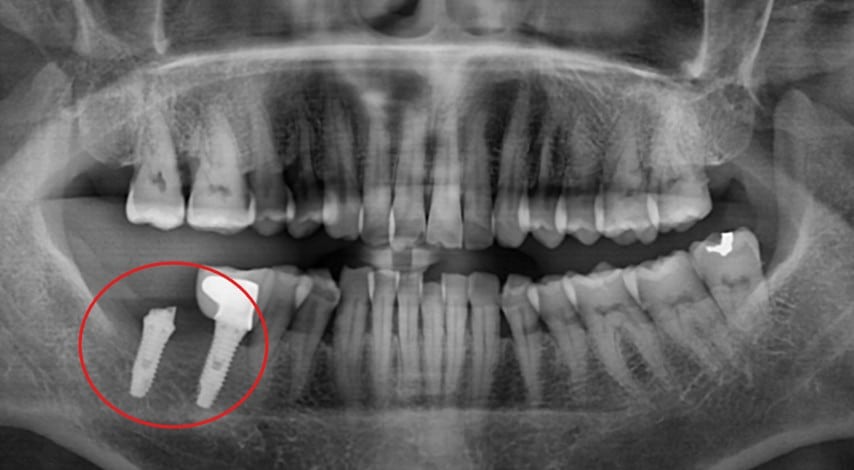

- Tooth site: Lower right #31 implant

- The abutment (connector) was fractured, leaving metal exposed above the gum line.

- The implant body remained stable, with no mobility.

- Mild soft tissue irritation observed due to the sharp fractured surface.

Figure 1: Clinical photos showing fractured abutment at #31 site